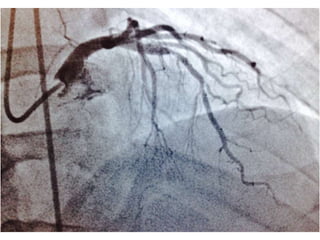

CASO CLINICO #3 MASCULINO 65 AÑOS DE EDAD DIABETES TIPO 2 DESDE HACE 15 AÑOS POBRE CONTROL METABOLICO DISLIPIDEMIA. OBESIDAD GRADO II. CUADRO CLINICO: ANGINA DE PECHO ATIPICA. CHEQUEO DE RUTINA. ECG DE REPOSO NORMAL. PRUEBA DE ESFUERZO POSITIVA Y PRECOZ PARA ISQUEMIA. TA 120/ 68 mm Hg. FC 67/min Fr 13/ min Glucosa en Ayunas 215 mg /dL. Colesterol total 260 mg/dL, LDL 135 mg d/L Creatinina 1.2 mg/dL EXAMEN FISICO ANODINO